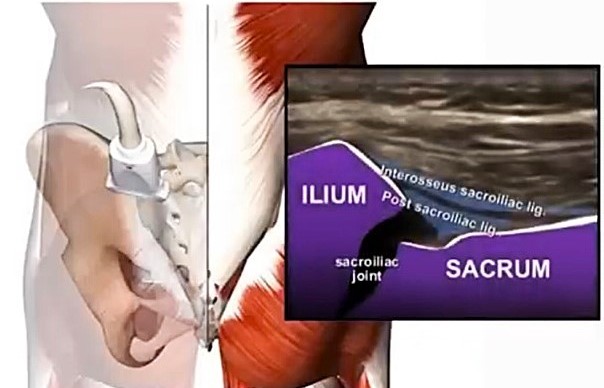

仙腸関節炎

腰痛の原因で多い仙腸関節痛に超音波ガイド下に仙腸関節に針を正確に刺入し薬剤を注入します